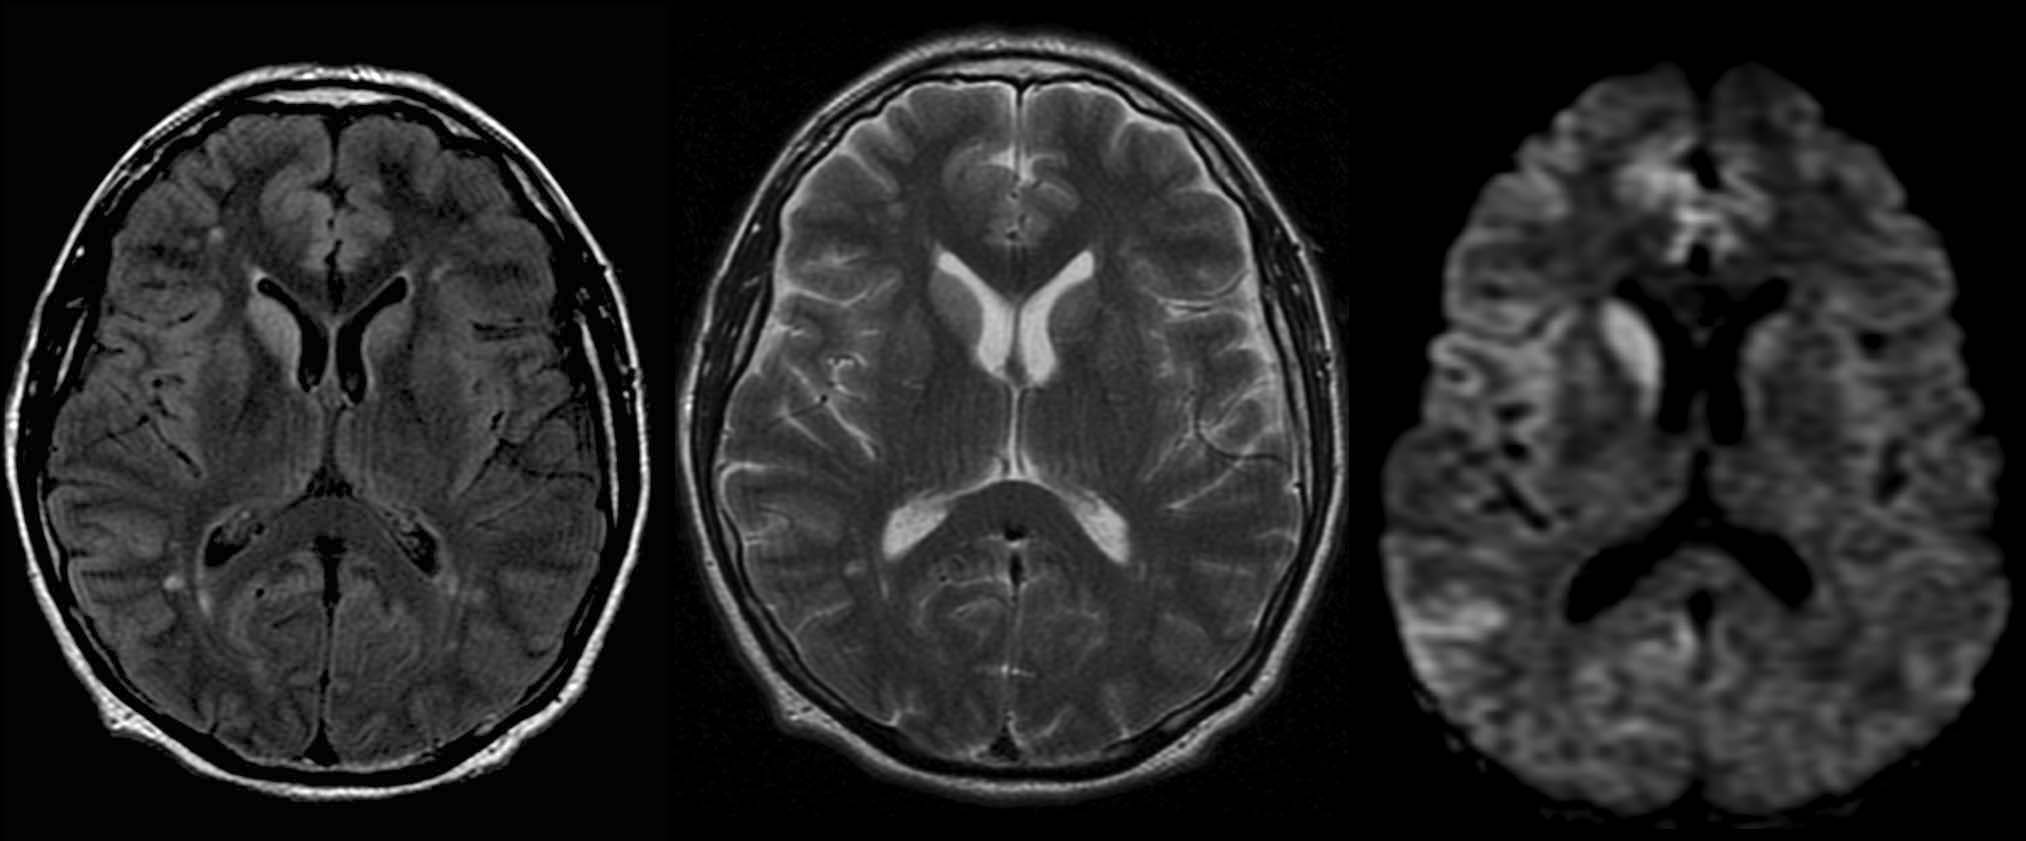

Paciente de 48 años con demencia rápidamente progresiva.

- D. Enfermedad de Creutzfeldt-Jacob con alteración de señal asimétrica en núcleo caudado y cortical frontotemporal.